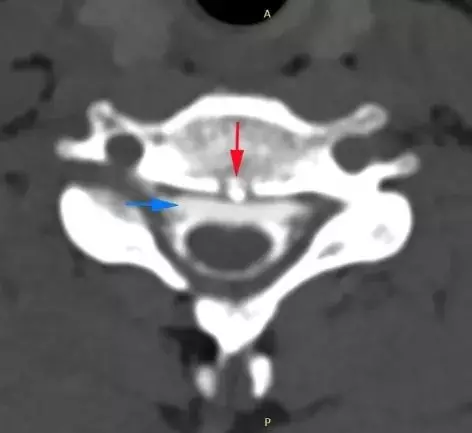

宋先生的脊柱磁共振檢查

可見第2、3胸椎之間有「骨刺」形成(紅箭頭)

刺破硬脊髓膜,造成腦脊液外漏(藍箭頭)

江女士的脊柱磁共振檢查

可見第1、2胸椎之間有「骨刺」形成(紅箭頭)

警惕腦脊液外漏、脊柱退變

此前,浙江大學醫學院附屬邵逸夫醫院神經內科曾接連接診了兩個年輕的「低頭族」,長時間低頭用電腦、玩手機 而頭痛難忍。經醫院檢查顯示,患者頸段椎間盤退變 ,形成骨刺並刺破了硬脊髓膜 ,造成了脊髓腦脊液滲漏 ,顱內壓力過低還造成了腦膜血管撕裂和硬膜下出血。